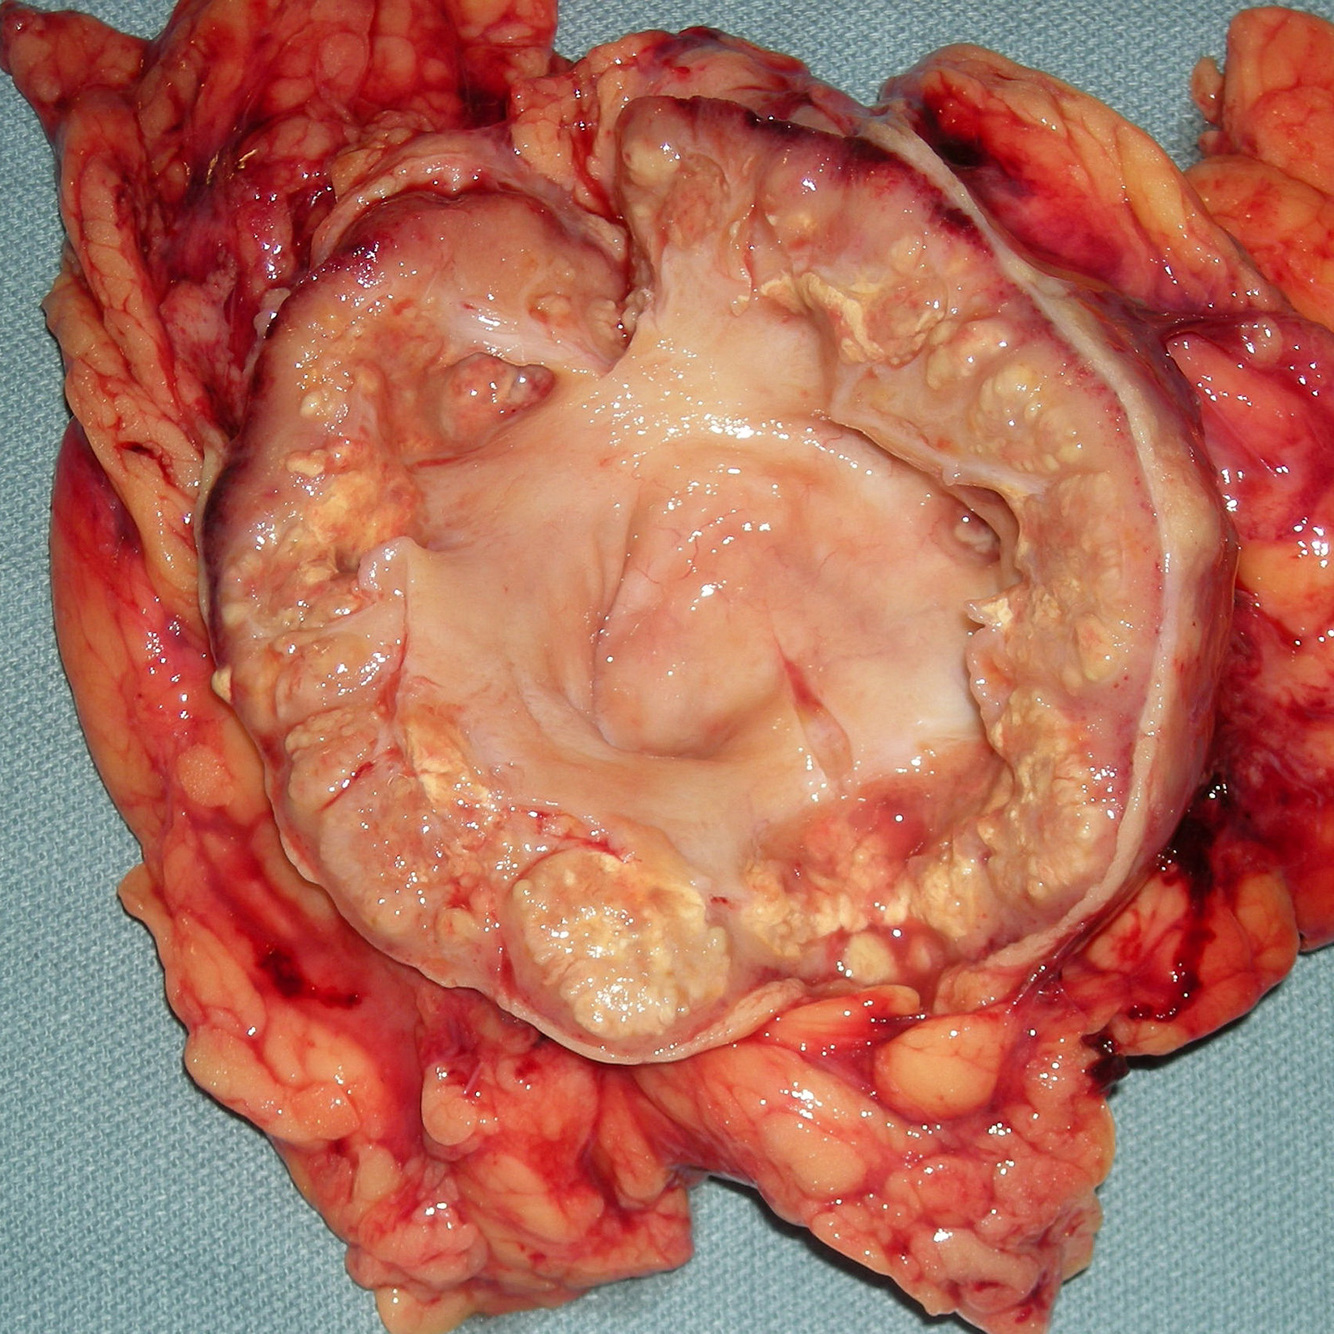

PATHOLOGY Specimen

What is this condition?

What is the cell type involved

What are the 2 forms?

What is the underlying condition a/w this?

Xanthogranulomatous Pyelonephritis (XGP)